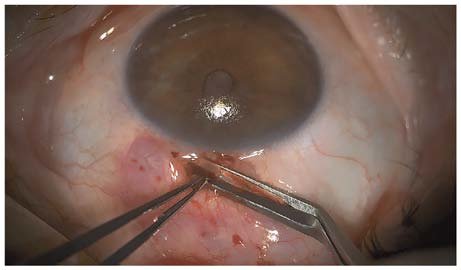

2. 홍채, 수정체, 혈액, 유리체 등으로 누공(sclerotomy site)이 막힌 경우

전방각 근처의 구조물들이 누공의 안구 내부 위치를 막는 경우,

막고 있는 원인이 되는 구조물들을 제거해주어야합니다.

홍채유착에 의해서 막힌 경우, 유착된 홍채를 다시 풀어주고,

혈액이나 유리체 등에 의해서 막힌 경우, Nd:YAG laser 등을 이용해서 누공부위를 다시 열어줄수 있습니다.